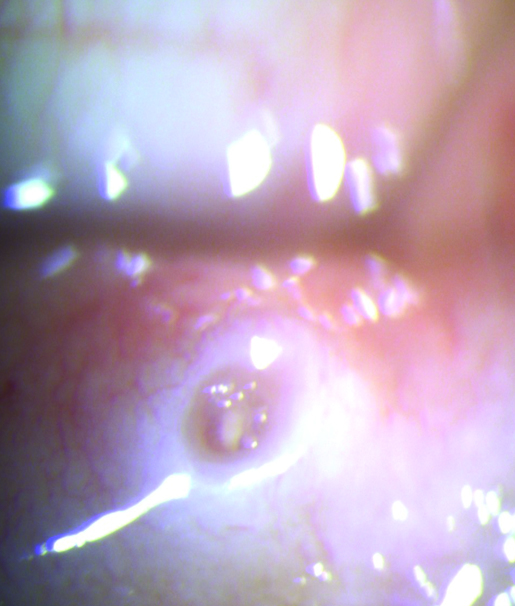

Con el rosa de bengala o la lisamina verde se puede determinar además el grado de fricción palpebral que se expresa al evertir el párpado superior y observar si el colorante tiñe el borde interno palpebral (Fig. 9).

Figura 9: Tinción con lisamina zona de fricción